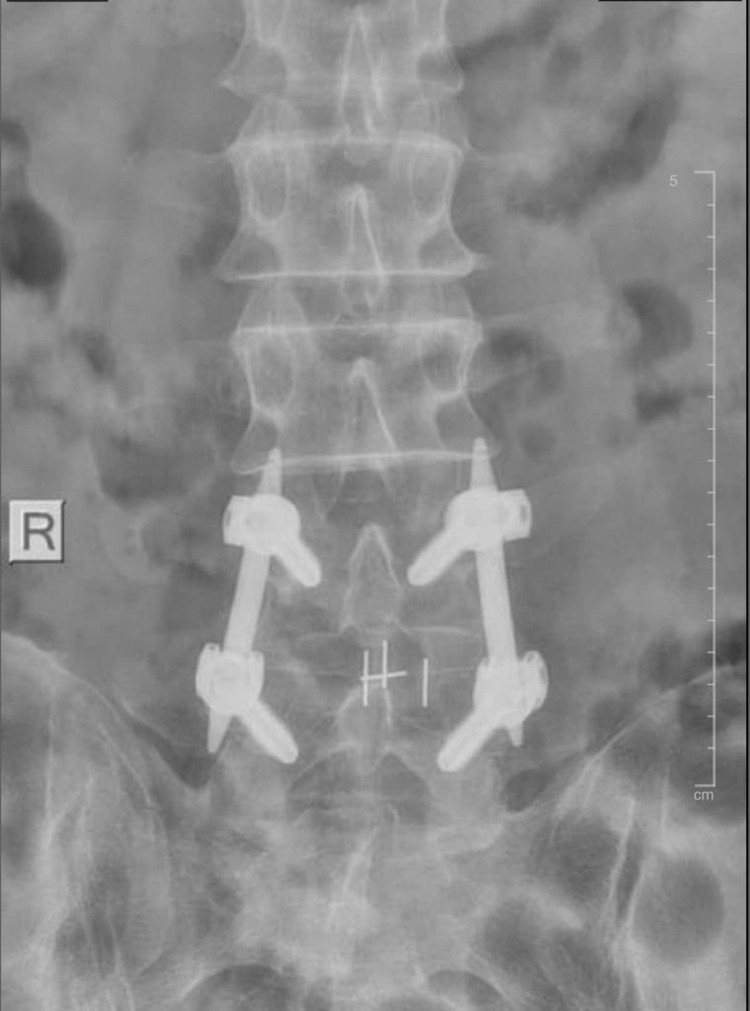

Hình ảnh MRI của bệnh nhân thực hiện bắt vít qua da. Ảnh BV

Điều trị thoát vị đĩa đệm bằng phương pháp bắt vít qua da giúp bệnh nhân có thể vận động sớm ngay sau mổ. Ảnh BV